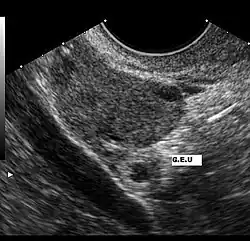

Eine Extrauteringravidität muss bei jeder Frau mit Bauchschmerzen oder vaginaler Blutung bei positivem Schwangerschaftstest angenommen werden. Eine Ultraschalluntersuchung, die außerhalb der Gebärmutter einen Fruchtsack mit fetalen Anteilen und Herzaktionen zeigt, ist beweisend für eine Extrauteringravidität.

Ein zu geringer Anstieg des β-hCG im Serum kann ebenfalls ein Hinweis auf eine ektope Schwangerschaft sein. Ab einem β-hCG-Wert von etwa 1500 IU/ml ist eine normale intrauterine Schwangerschaft im Ultraschall mit hoher Wahrscheinlichkeit darstellbar. Zeigt eine hochauflösende transvaginale Sonografie bei einem solchen Wert keine intrauterine Schwangerschaft, muss eine Extrauteringravidität in Betracht gezogen werden.